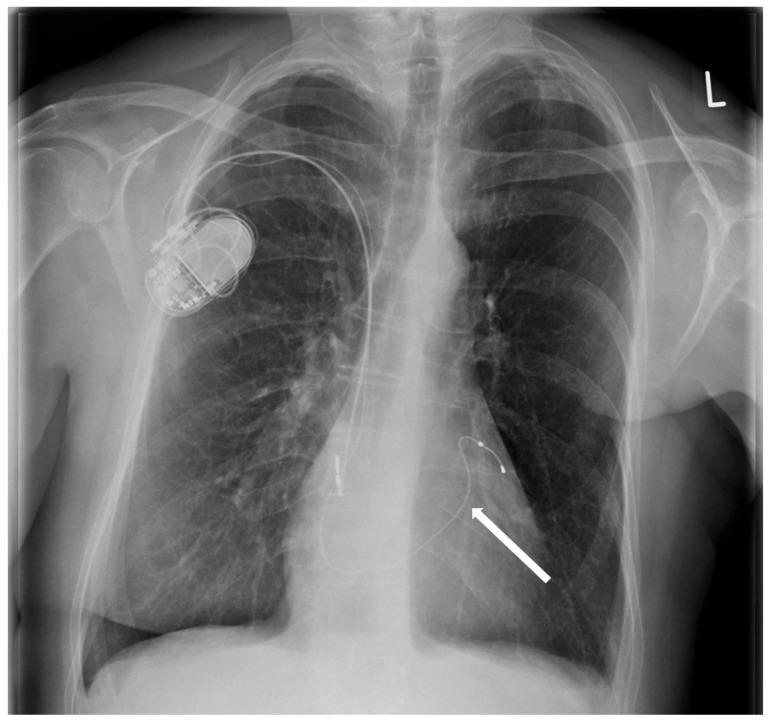

Cardiological and oncological patients comprise the majority of patients admitted to the emergency unit with chronic or acute conditions that are the dominant cause of death worldwide. However, electrotherapy and implantable devices (pacemakers and cardioverters) improve the prognosis of cardiological patients. We present the case report of a patient who, in the past, had a pacemaker implanted due to symptomatic sick sinus syndrome (SSS) without removing the two remaining leads. Echocardiography revealed severe tricuspid valve regurgitation. The tricuspid valve septal cusp was in a restricting position due to the two ventricular leads passing through the valve. A few years later, she was diagnosed with breast cancer. We present a 65-year-old female admitted to the department due to right ventricular failure. The patient manifested symptoms of right heart failure, predominated by ascites and lower extremity edema, despite increasing doses of diuretics. The patient underwent a mastectomy two years ago due to breast cancer and was qualified for thorax radiotherapy. A new pacemaker system was implanted in the right subclavian area as the pacemaker generator occupied the radiotherapy field. In the case of right ventricular lead removal and the need for pacing and resynchronization therapy, guidelines allow a coronary sinus for LV pacing to avoid passing the leads through the tricuspid valve. We facilitated this approach in our patient, suggesting that the percentage of ventricular pacing was very low.

心脏病患者和肿瘤患者占因慢性或急性疾病入住急诊科患者的大多数,这些疾病是全球主要的死亡原因。然而,电疗法和植入式设备(起搏器和心脏复律器)可改善心脏病患者的预后。我们报告一例患者,该患者过去因症状性病态窦房结综合征(SSS)植入了起搏器,但未取出剩余的两根导线。超声心动图显示严重三尖瓣反流。由于两根心室导线穿过瓣膜,三尖瓣隔叶处于受限位置。几年后,她被诊断出患有乳腺癌。我们介绍一名65岁女性因右心室衰竭入住该科室。尽管利尿剂剂量不断增加,但患者仍表现出以腹水和下肢水肿为主的右心衰竭症状。该患者两年前因乳腺癌接受了乳房切除术,并符合胸部放疗条件。由于起搏器发生器占据放疗区域,在右锁骨下区域植入了新的起搏器系统。在需要移除右心室导线并进行起搏和再同步治疗的情况下,指南允许通过冠状窦进行左心室起搏,以避免导线穿过三尖瓣。我们在患者中采用了这种方法,表明心室起搏的百分比非常低。